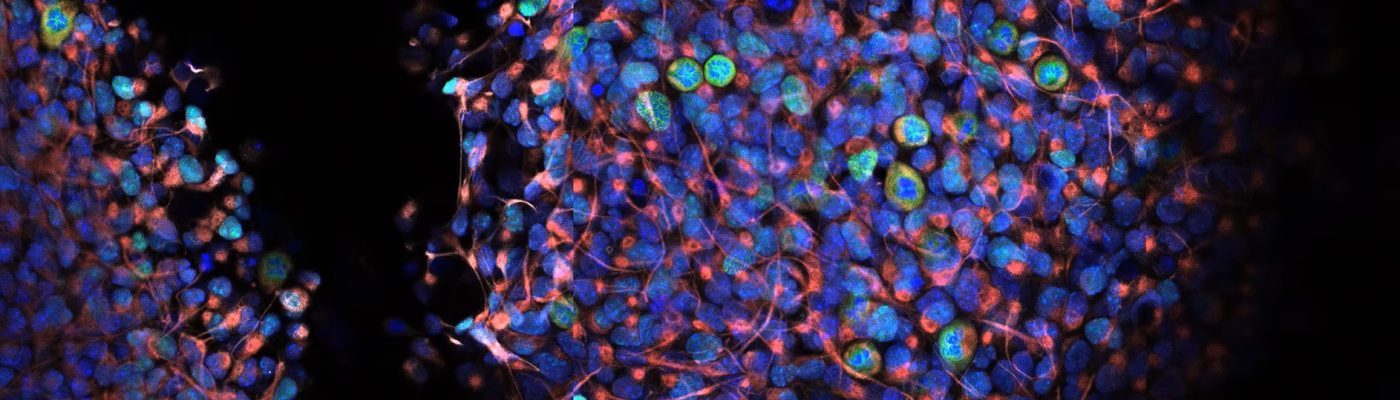

There is growing awareness that a common hallmark of neurological and psychiatric diseases is synaptic dysfunction. The Unit’s main focus is to evaluate how neurons, glial cells, and synapses are modulated, and how these processes are altered in disease states or restored by potential therapeutics. Current research addresses dysfunctions in various types of epilepsy, synaptic circuitry remodeling after stroke and seizures, synaptic reorganization following chronic drug abuse and/or depression, and functional alterations of neurons, glial cells, and synapses at the onset of neurodegenerative diseases such as amyotrophic lateral sclerosis, multiple sclerosis, and Alzheimer’s disease.